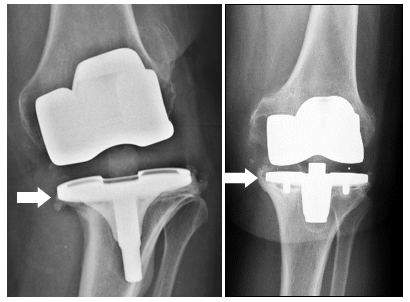

COMMON REASONS for replacing a knee prosthesis are, in addition to infection, instability or persistent pain.

DURING A RE-OPERATION OF THE KNEE, special implants are often necessary to replace defective ligaments (using a so-called coupled prosthesis) or to RECONSTRUCT DEFECTS IN THE BONE (using augments or bone replacement MATERIAL).